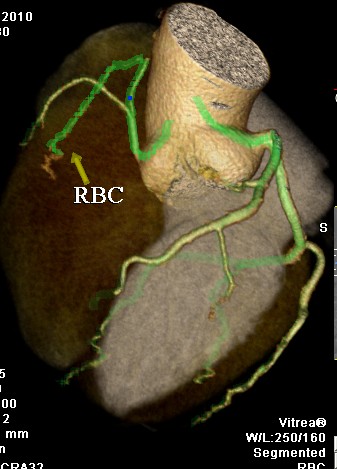

标题: CT24400:患者54岁,心前区不适进行心脏冠脉造影检查。 [打印本页]

标题: CT24400:患者54岁,心前区不适进行心脏冠脉造影检查。

患者54岁,心前区不适进行心脏冠脉造影检查。高手看看有问题没有?

图像很漂亮,好像未见异常